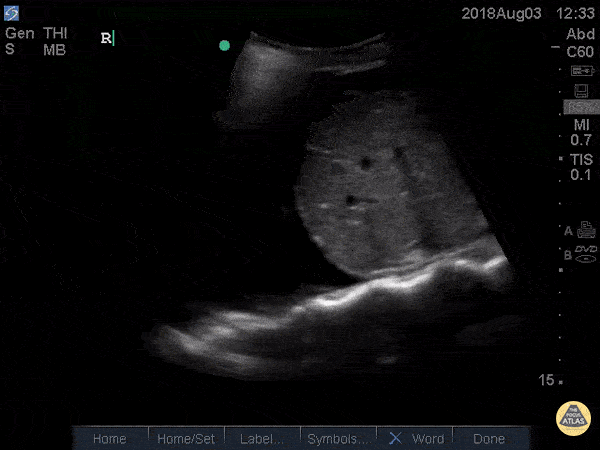

🫁 Consolidation (syndrome alvéolaire)

Substitution de l’air alvéolaire par du liquide ou de l’inflammation : le parenchyme prend un aspect tissulaire (« hépatiforme »).

Signes échographiques

- Aspect tissulaire : zone échogène, granuleuse, proche de l’aspect du foie.

- Bronchogrammes aériques : air circulant dans les bronches visibles au sein d’une condensation.

- Bronchogrammes dynamiques : signal Doppler couleur avec la respiration → pneumonie (voies aériennes perméables).

- Bronchogrammes statiques : immobiles → atélectasie (obstruction bronchique).

- Poumon “déchiqueté” : limite irrégulière entre le poumon aéré et la consolidation.

- Épanchement pleural associé fréquent, souvent visualisé comme une lame anéchogène au-dessus du diaphragme.

Étiologies courantes – Pneumonie, atélectasie, aspiration, contusion pulmonaire.